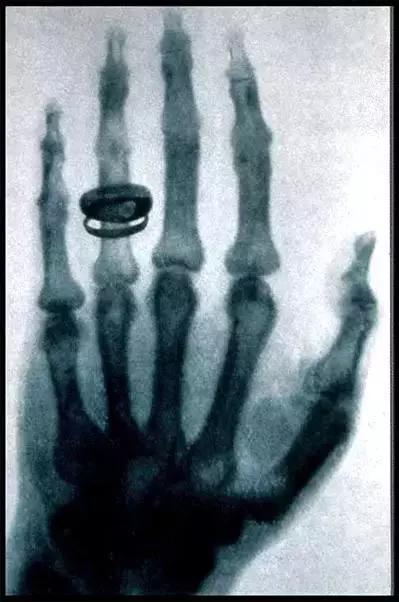

X射线是著名的伦琴发现的,它是影响医学的开端。X线发明的故事大家也都熟悉,伦琴在一个偶然的机会下从X射线现中看见了自己手的骨骼,所以说X射线主要是用来看骨头。

此外还有一个最常见的作用是拍胸片,主要是粗略的看一下肺部和心脏的轮廓,诸如肺部感染、先天性心脏病导致的心脏大小形态变化、肺癌之类的典型的影像表现,x片能够做到一目了然。